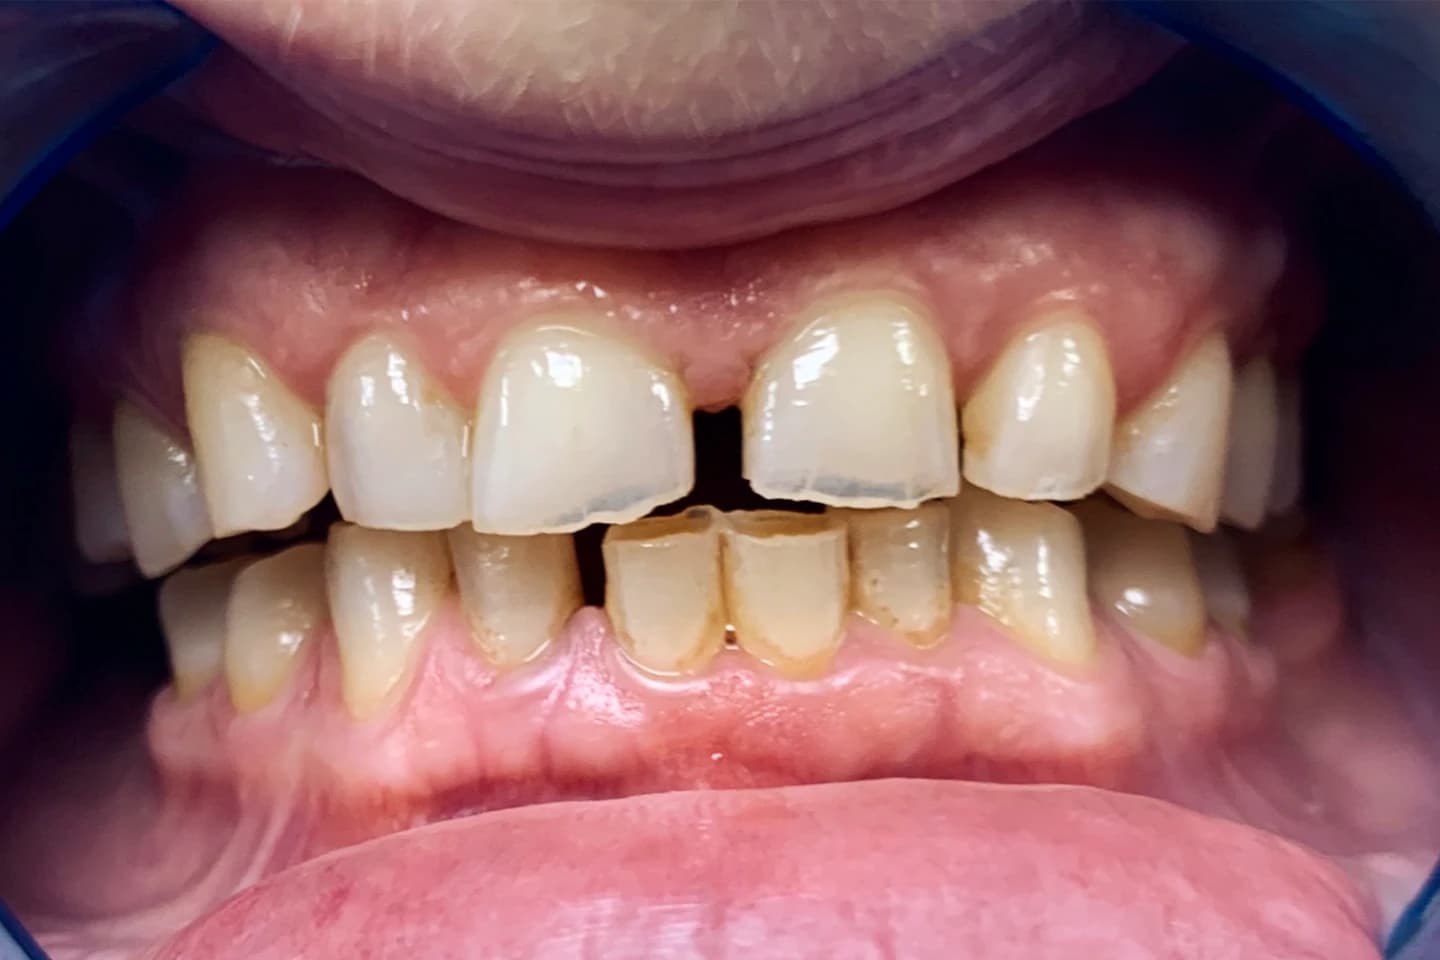

Osmeh i oblik zuba slike - pre i posle

Stomatološka ordinacija Marco Dental Tourism svakodnevno stvara neverovatne transformacije osmeha. Pogledajte galeriju naših radova i uverite se u moć stomatologije!

Želimo i vama da pomognemo da postignete savrršen osmeh kada su u pitanju položaj i oblici zuba. Zato smo prikupili inspirativne priče i fotografije zuba naših pacijenata, koje će vam pokazati šta je sve moguće uz stručnost i posvećenost našeg tima.